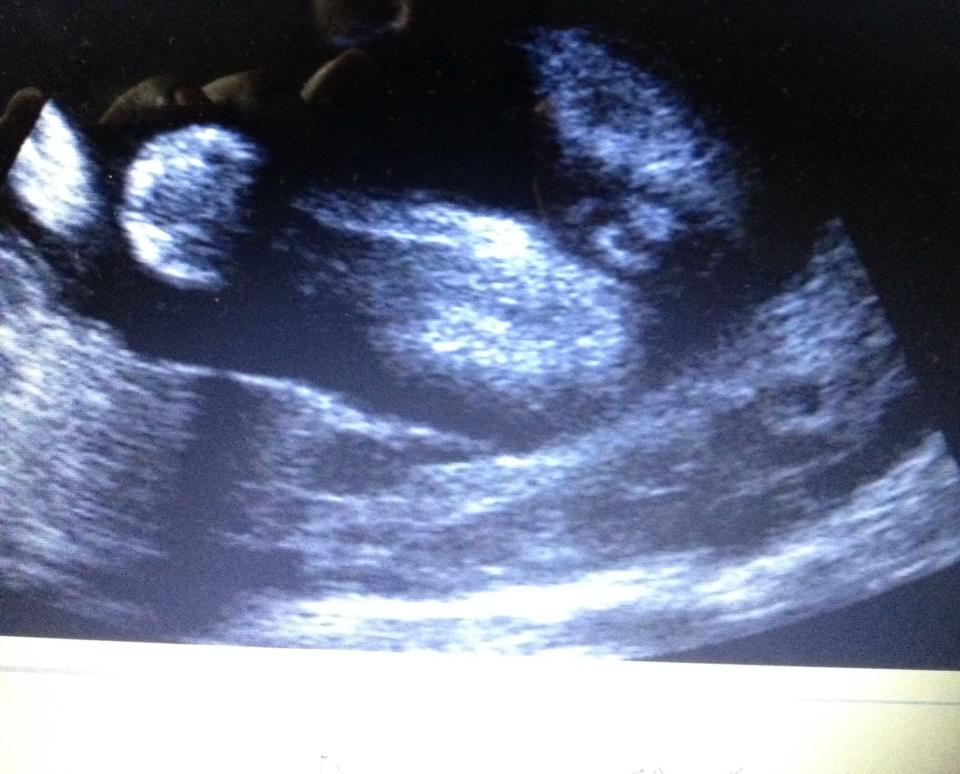

Hi, I've been told it's a boy and a girl... which is it? haha

These scans were taken at 24 weeksAttachment 28867Attachment 28868Attachment 28869

God I hope you're right haha! Depending on the angle it looked girl and other angles it looked boy.... At my 16w they said boy, 19w they said girl "she saw 3 lines" and now these pix at 24weeks lol (I might add - the tech didn't take these pix, I did with the dvd she gave me of the area..).

I just guessed boy as looks like scrotum bits! Im no expert but I know number 2 of mine had visible balls [emoji23][emoji16] hopefully they're swollen girlie bits as the others have said! How confusing for you to be told different genders [emoji30] surely the later one would be more accurate? X

I also guess girl, at this stage you would see the penis for sure!! How strange the tech could not see / show you the gender at this point. But iI think if it were a boy you would definitely see a penis

Could it be a small penis or a huge clitoris..? lol

I'm thinking labia